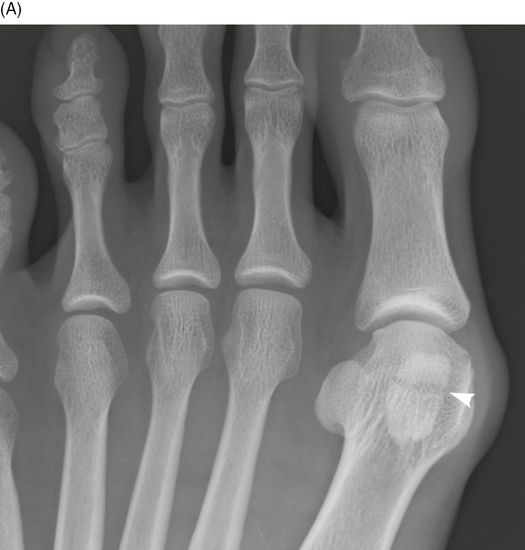

Image Sesamoid Fracture Radiograph MSD Manual Professional Edition Stress Fracture Sesamoid Symptoms Pain from a sesamoid injury is focused under the big toe on the ball of the foot. With sesamoiditis or a stress. Most patients with a sesamoid fracture describe a deep, achy,. With sesamoiditis, pain may develop gradually. Fractures may occur in the two small round bones at the base of the big toe (sesamoid bones). the medial (ie,. Stress Fracture Sesamoid Symptoms.